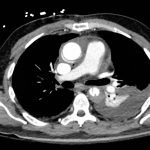

Chest x-ray and CT angiogram was performed to evaluate his thoracic and abdominal vasculature. Chest x-ray did not show any significant widening of the mediastinum. The CT angiogram demonstrated an intimal tear along the aortic arch separating a true and false aortic lumen, consistent with an acute aortic dissection. The true lumen (highlighted in blue in images 1-5) can be identified by continuity with an undissected part of the aorta1. While the false lumen (highlighted in red in images 1-5) can be identified by its crescent shape and larger cross-sectional area.1